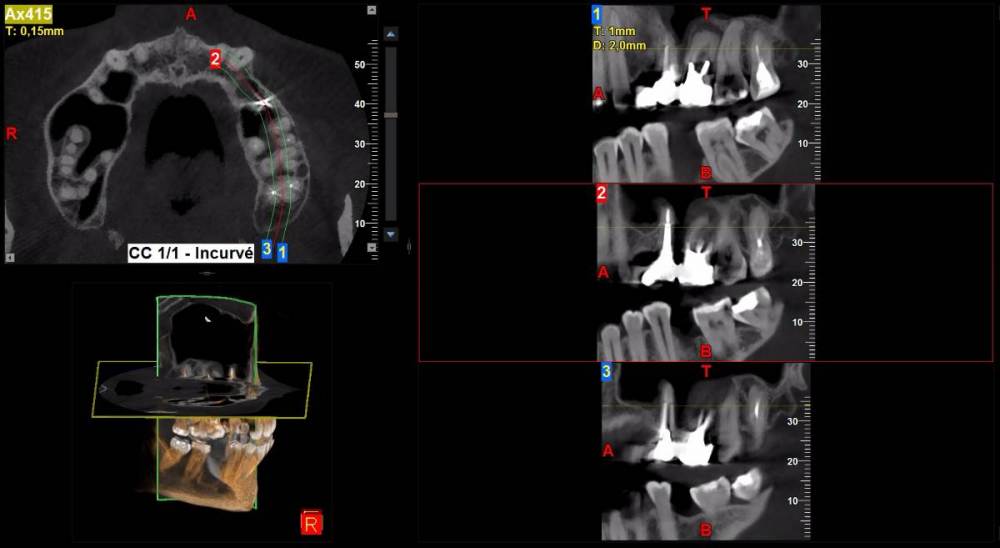

DeLaMer Опубликовано 11 августа, 2021 Поделиться Опубликовано 11 августа, 2021 (изменено) Добрый день уважаемым докторам-участникам форума. Хотелось бы, по возможности, получить экспертное мнение по поводу моей проблемы. На верхней челюсти есть мост, объединяющий 6й, 5й и отсутствующий 4 зубы (если я правильно понимаю нумерацию, это должны быть 24, 25, 26). В начале июня на десне открылся свищ с гноем (абсцесс, но, видимо, не острый, кроме периодического надувания гнойного шарика ничего больше не происходило). По этом поводу мой лечащий врач поднял КТ, которое было сделано осенью до того по другому поводу и обнаружила воспаление одного из корней 6-го зуба. При этом она высказала соображение, что может быть здесь поможет резекция верхушки того самого корня. Один из хирургов, с которым я консультировалась по этому поводу, сказал, что на его взгляд резекция возможна. Другой - что воспаление проявляется не только на одном корне, а на двух и по его мнению сделать тут ничего нельзя, только распиливать коронку и удалять 6й зуб. Я была бы крайне благодарна, если бы уважаемые специалисты высказали свое мнение по этому поводу, потому что при равноценных двух противоположных мнениях мне даже не понятно с чего начинать. Прикрепляю ссылку на файл КТ на своем дропбоксе. Огромное спасибо за помощь https://www.dropbox.com/s/fkv8cvqqq6grgpe/Sergeeva A..zip?dl=0 Изменено 11 августа, 2021 пользователем DeLaMer Ссылка на комментарий

Irouil Опубликовано 12 августа, 2021 Поделиться Опубликовано 12 августа, 2021 По представленным средам создаётся впечатление, что у зуба фактически разрушено соединение между корнями. Риски того, что он под нагрузкой раскроется в любой момент, достаточно высоки Ссылка на комментарий

АнтонТЛТ Опубликовано 13 августа, 2021 Поделиться Опубликовано 13 августа, 2021 (изменено) Там всё ок с фуркацией и вкладка коротконогая. Просто на КТ очень много артефактов. Изменено 13 августа, 2021 пользователем АнтонТЛТ Ссылка на комментарий